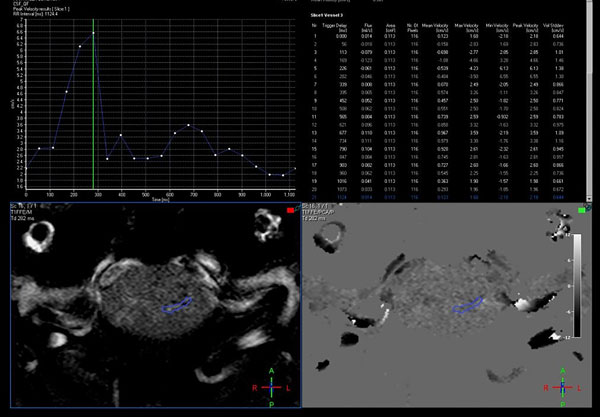

La valoración cuantitativa requiere un postproceso para medición de flujo en estaciones de trabajo con software dedicado, las cuales permiten la evaluación de la curva obtenida durante todo el ciclo cardíaco, que es característicamente bifásica, con los respectivos cálculos de los valores de velocidad pico, media y stroke volume.

Figura 2: Evaluación cuantitativa en RM con técnica de contraste de fase, mediante la adquisición en el plano axial, perpendicular al sitio de mayor compromiso del pasaje de LCR, con un área de interés que muestra las curvas de flujo y un aumento de la velocidad pico hasta 6,55 cm/segundo.